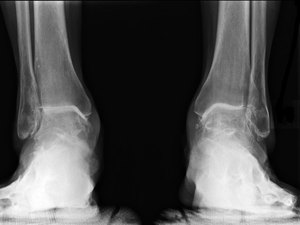

На каждой стадии заболевания наблюдаются различные симптомы, который можно определить в том числе и по рентгеновским снимкам.

Болевые симптомы если и имеют место, то проявляются в незначительной степени. В этот момент артроз колена выглядит на рентгеновском снимке в виде небольших неровностей на хрящевой ткани и поверхности костей.

Может наблюдаться также незначительное сужение просвета между костьми. На этом этапе диагностировать патологию крайне сложно, поэтому обязательным является прохождение рентгенографии.

Рентгенограмма способна показать глобальные изменения хрящевой ткани, поверхности сустава, нехарактерные наросты. О-образное или икс-образное искривление доводит человека до инвалидности.

Основной метод диагностики гонартроза – рентгенография сустава (при этом на первой стадии патология может быть и не выявлена). Таких снимков может быть несколько, чтобы проследить динамику развития заболевания. Помимо рентгена могут быть назначены МРТ или компьютерная томография.